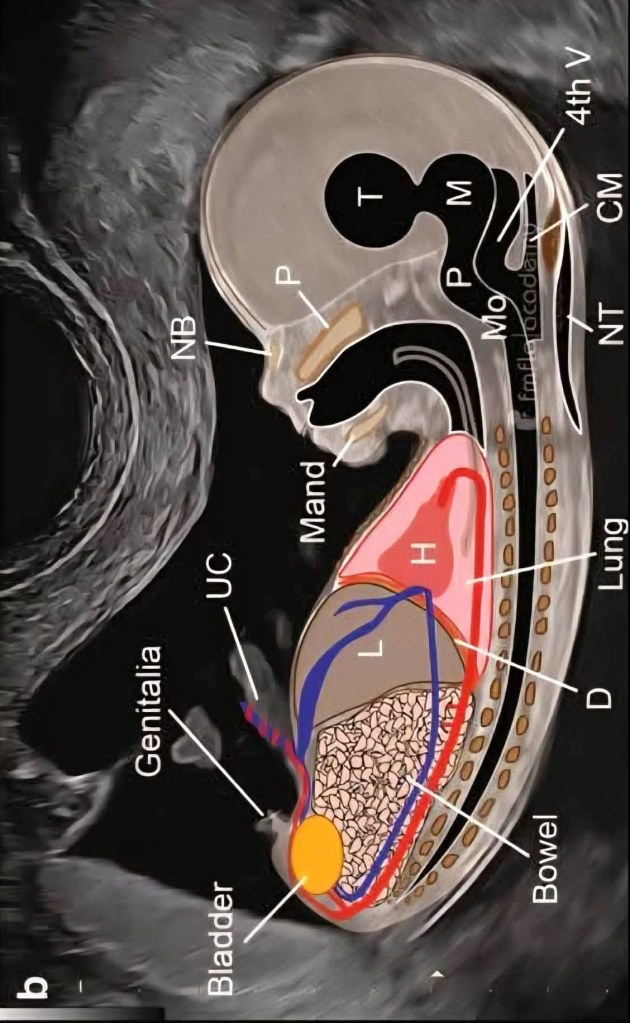

T= Talamo, M = Mesencéfalo, P= Protuberancia, Mo= Medulo Oblonga, CM= Cisterna Magna,

4th= Cuarto Ventriculo, NT= Traslucencia Nucal, NB= Hueso Nasal, P= Paladar, Mad= Maxilar Inferior

Lung= Pulmón, H= Corazón, D= Diafragma, L= Hígado, Bowel= Instestinos, UC= Cordón Umbilical

Genitalia= Genitales, Bladder= Vejiga